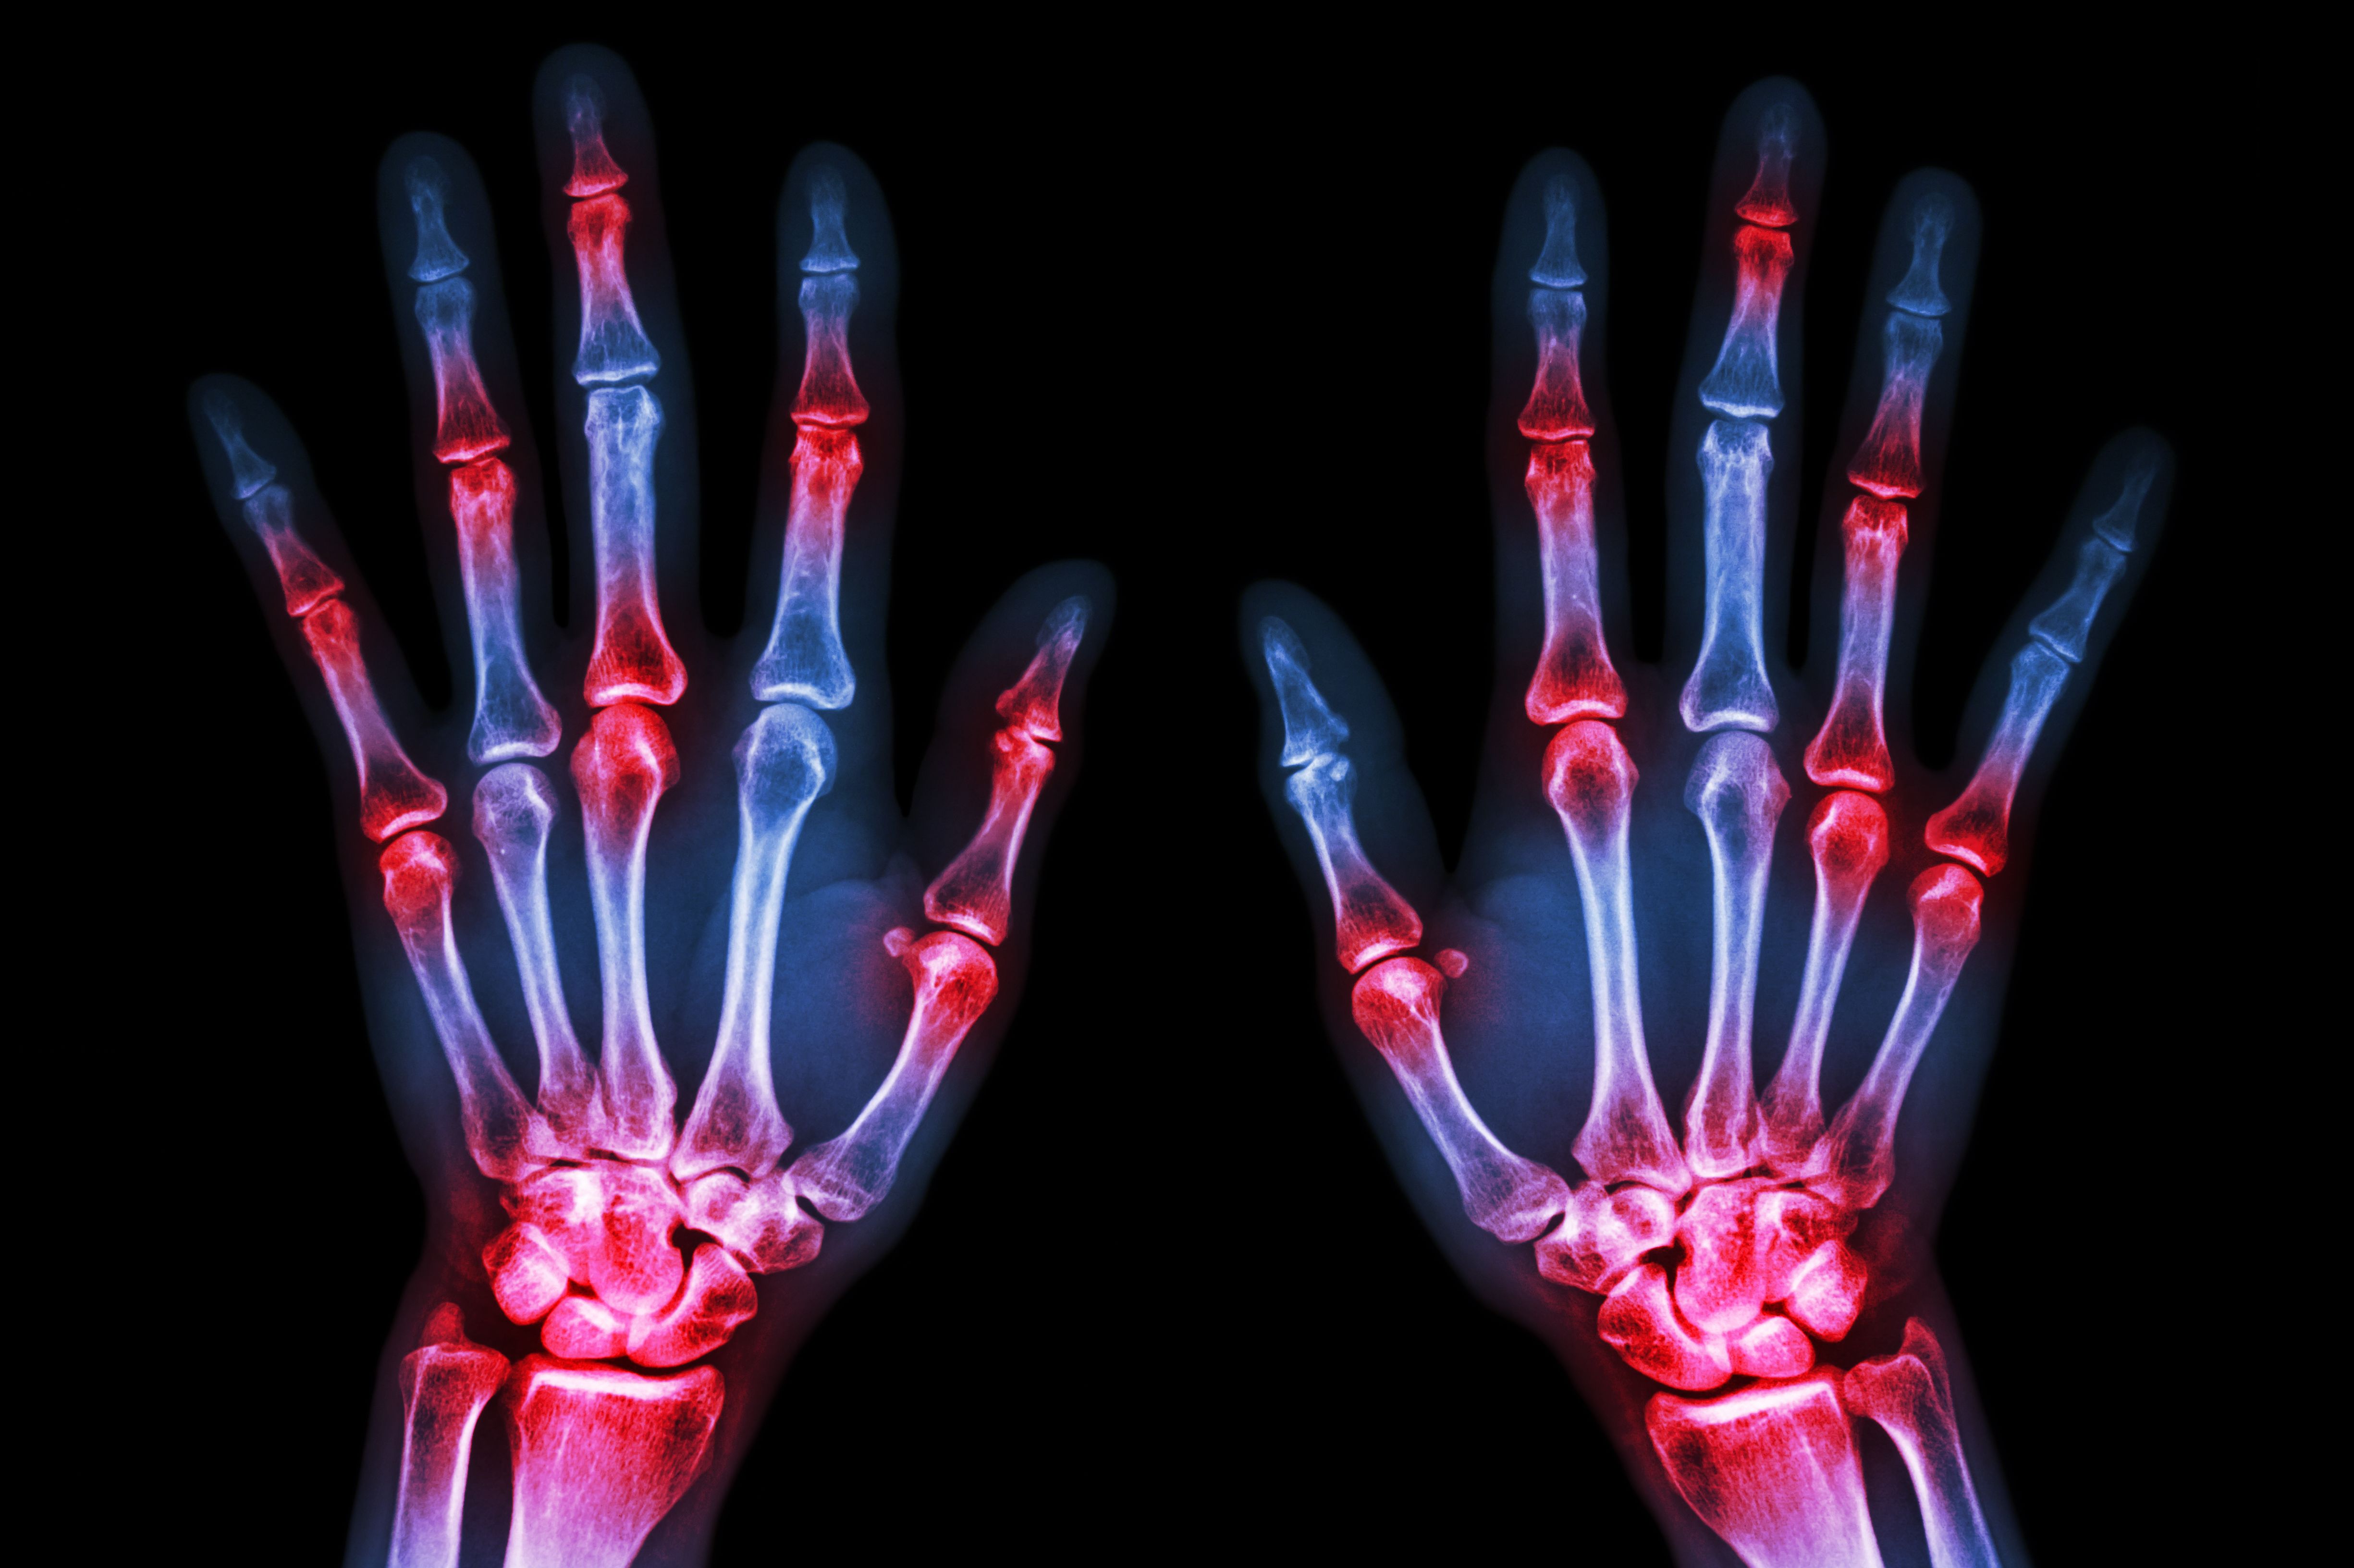

Rheumatoid arthritis is a common inflammatory joint disease. A feature of this disease is the increased fusion of endogenous immune cells (macrophages) to form so-called osteoclasts, which attack and break down bone tissue.

Microscopic image of osteoclasts that have developed in cell culture